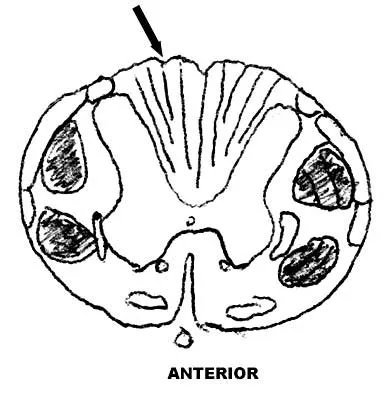

Figure 9 shows a cross-sectional view of the spinal cord at the lower cervical level. Injury to the structure indicated by the black arrow will lead to what neurologic deficit?